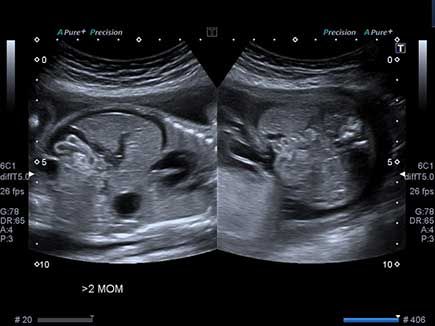

Challenge your diagnostic skills: Can you identify this cardiac defect?